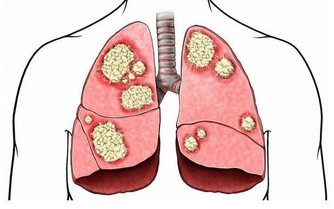

4、心血管及脂代謝障礙

許多女性朋友在更年期還往往會產生心血管症狀以及脂代謝障礙的情況,甚至還有可能會引起冠心病、糖尿病等嚴重疾病。